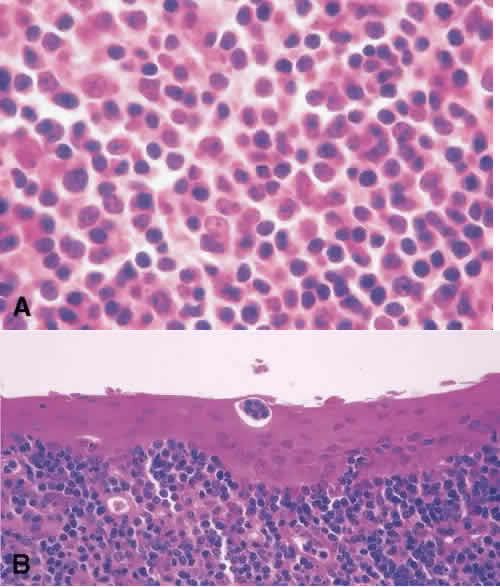

Benign and malignant lymphoid proliferation may present clinically as a relatively flat lesion with a smooth surface and salmon pink appearance.84 Tissue biopsy is necessary to categorize them because there is a spectrum of lymphoproliferative lesions that can occur in the conjunctiva. They can be benign as reactive lymphoid hyperplasia or malignant as non-Hodgkin lymphoma. Hodgkin lymphoma of the conjunctiva is rare. Marginal zone B-cell lymphoma is the most common type in the conjunctiva. Lymphomas occurring in the conjunctiva have a relatively good prognosis. Systemic lymphoma can develop concurrently with reactive lymphoid hyperplasia (25% of cases) or malignant lymphoma (50%–75% of cases).84 Ancillary tests are recommended in classifying benign versus malignant lymphoproliferative lesions. Immunophenotyping with flow cytometry or immunoperoxidase staining may show monoclonality. A monoclonal lesion is suggestive of a malignant process. However, a benign lesion can harbor a clone, and the results of flow cytometry should be interpreted in light of the histology.85Histologically, reactive lymphoid hyperplasia is characterized by the presence of reactive endothelial cells, follicular centers with mitotic figures limited to the follicle. Tingible body macrophages may also be present (Fig. 15). In marginal zone B-cell lymphoma, the follicles are atretic, and tingible body macrophages are absent. The lymphoid tumor cells can be present in the conjunctival epithelium and are characterized as lymphoepithelial lesions(Fig. 16).

Fig. 15. Biopsy specimen of a bulbar conjunctival mass. The substantia propria contains a follicle of large lymphocytes surrounded by a rim of small lymphocytes consistent with lymphoid hyperplasia of the conjunctiva.

Fig. 16. Histology of marginal zone B-cell lymphoma of the conjunctiva shows medium-sized, atypical lymphocytes infiltrating the substantia propria of the conjunctiva. A nest of malignant lymphocytes is identified in the conjunctival epithelium consistent with a lymphoepithelial proliferation.